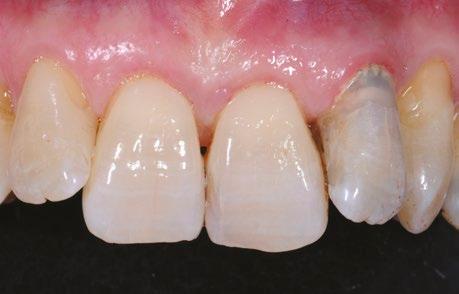

Jak už bylo dříve zmíněno, diagnostická fáze hraje zásadní roli, a proto musí být provedena s maximální

pečlivostí. Zahrnuje nejen posouzení stavu jednotlivých zubů, ale také analýzu rizikových faktorů spojených s celkovým zdravotním stavem a životním stylem pacienta. Pro ilustraci této problematiky ukazují obrázky 1.1 a 1.2 diagnosticko-terapeutický postup, který navrhuje možné léčebné řešení a aktivně zapojuje pacienta do rozhodovacího procesu. Tento přístup zajišťuje, že je pacient plně informován o dostupných terapeutických možnostech, což mu umožňuje činit kvalifikovaná rozhodnutí o svém orálním zdraví.